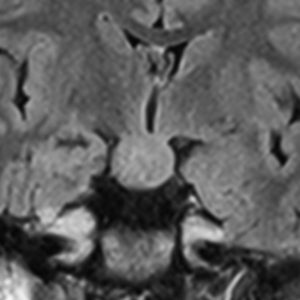

幼児期にgelastic seizureで発症

2歳でgelastic seizureを発症,6歳で思春期早発となりました

左視床下部に限局して柄を有するものです,左視索と乳頭体との境界はありません

おそらく左視床下部の機能低下と難治性の発作が原因で,左大脳半球の萎縮(あるいは発達不良)が認められます